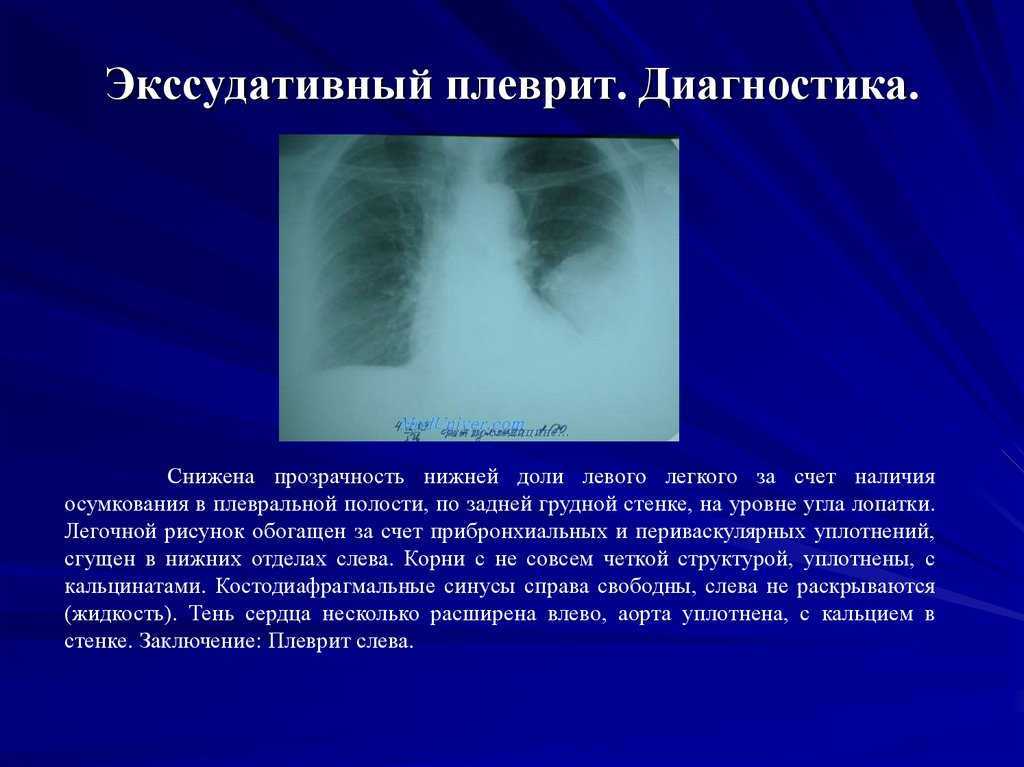

Диагностика плеврального выпота: что нужно знать